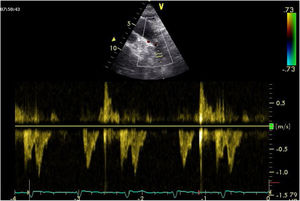

| C.2.2. Índice de Tei o índice de funcionamiento miocárdico (IFM) o índice de performance miocárdico. Permite hacer una estimación global tanto de la función sistólica como de la diastólica ventricular (derecha o izquierda). Está basado en la relación del trabajo eyectivo y no eyectivo del corazón. Se define como la relación entre la suma del tiempo de relajación isovolumétrica y de la contracción isovolumétrica, dividido por el tiempo eyectivo (índice Tei =TRIV +TCIV) /TE). Índice pronóstico poco utilizado en la práctica clínica, tendiendo a aumentar en caso de disfunción ventricular sistólica y/o diastólica.Es un método simple de obtener, reproducible, independiente de la frecuencia cardíaca y de la presión arterial, y es útil para estimar la severidad y el pronóstico de la afectación miocárdica y como predictor de disfunción postoperatoria ventricular izquierda en pacientes con insuficiencia mitral con fracción eyectiva aparentemente normal (4). Un índice Tei preoperatorio >0,5 permite predecir la disfunción postoperatoria del VI en pacientes con IM con FE aparentemente normal. Podemos medirlo mediante Doppler tisular a nivel del anillo mitral (A) o Doppler espectral pulsado, colocando el volumen de muestra amplio entre el TSVI y la mitral (B). El DTI puede utilizarse también para medir el índice Tei del VD, teniendo en cuenta que el TRIV del VD es prácticamente inexistente en el VD normal. Es un parámetro no influido por la frecuencia cardiaca ni la precarga que ha demostrado correlación con la severidad y el pronóstico de diversas patologías que afectan al VD. Su valor normal por DTI es de 0,39, considerándose patológico cuando es superior a 0,55. | ||